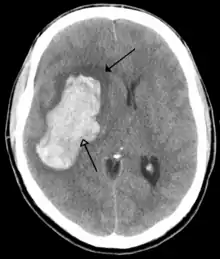

Ictus hemorrágico

Se deben a la rotura de un vaso sanguíneo encefálico debido a un pico hipertensivo o a un aneurisma congénito. Pueden clasificarse en: intraparenquimatosos y hemorragia subaracnoidea.

Las causas más frecuentes en la hemorragia cerebral son la hipertensión arterial y los aneurismas cerebrales.[32]

La hemorragia conduce a ictus a través de dos mecanismos. Por una parte, priva de riego al área cerebral dependiente de esa arteria, pero por otra parte, la sangre extravasada ejerce compresión sobre las estructuras cerebrales, incluidos otros vasos sanguíneos, lo que aumenta el área afectada. Ulteriormente, debido a las diferencias de presión osmótica, el hematoma producido atrae líquido plasmático, con lo que aumenta nuevamente el efecto compresivo local. Es por este mecanismo por lo que la valoración de la gravedad y el pronóstico médico de una hemorragia cerebral se demora 24 a 48 horas hasta la total definición del área afectada.